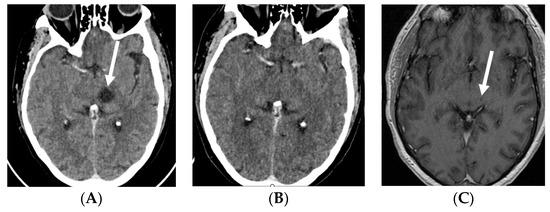

2.1. Case 1

2.2. Case 2